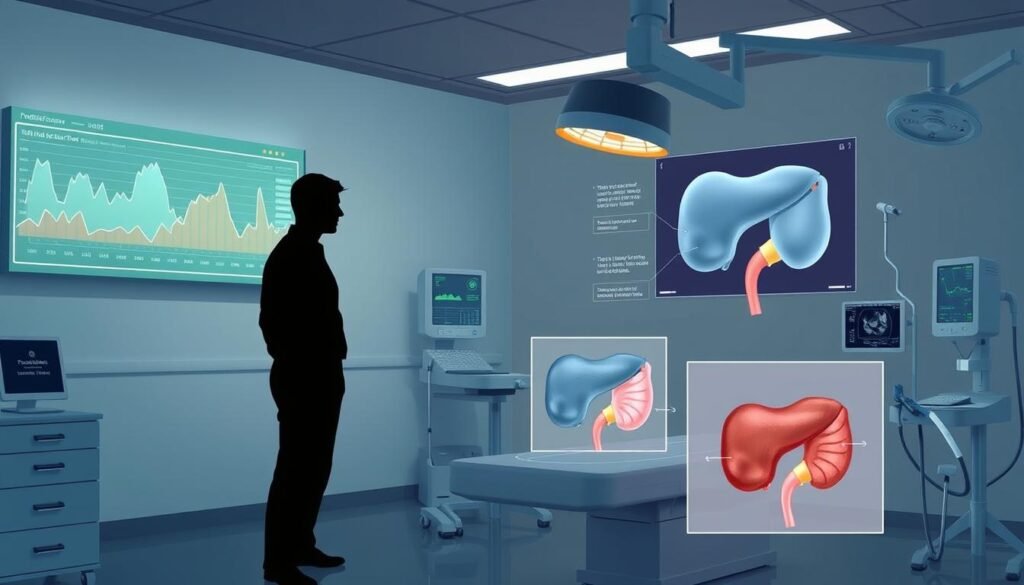

Advances in Diagnostic Technology

Technology has made prostate cancer tests better. For example, genetic testing can reveal how aggressive the cancer is. This helps in choosing the right treatment.

Better imaging makes it easier to see the prostate without surgery. This progress means doctors can offer patients care that fits them best. Thus, the way we find and treat prostate cancer is always improving, thanks to new tech.

Treatment Options for Prostate Cancer

Active Surveillance vs. Immediate Treatment

Active surveillance is best for low-risk, slow-growing prostate cancer. It means you can wait before starting heavy treatments. Doctors keep a close eye on the cancer with PSA tests and biopsies. If the cancer grows, you can then look at other treatments.

Medications and Surgical Treatments

Choosing between surgery or medication depends on many things. Surgeries can mean removing the prostate. Medications, like hormone therapy, focus on slowing the cancer. Each choice has its own pros and cons. This makes a personal treatment plan very important.